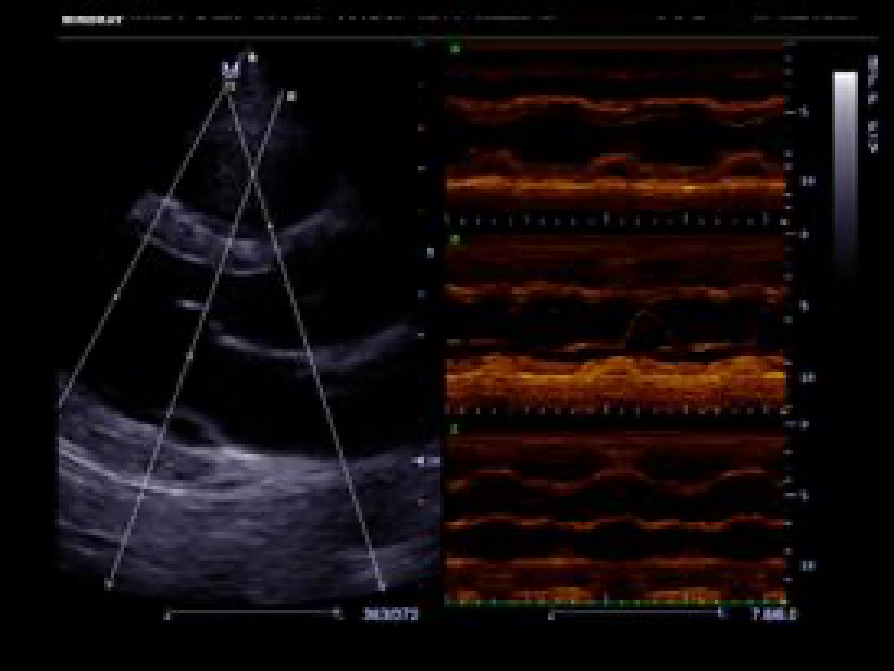

Tissue Doppler Imaging allows you to quantitatively evaluate local myocardial movement and function, providing complete TDI modes for faster and direct diagnoses.

Accurately evaluate myocardial motion at different phases, and simultaneously determine myocardial synchronization. High frame-rate providing you with accurate results.